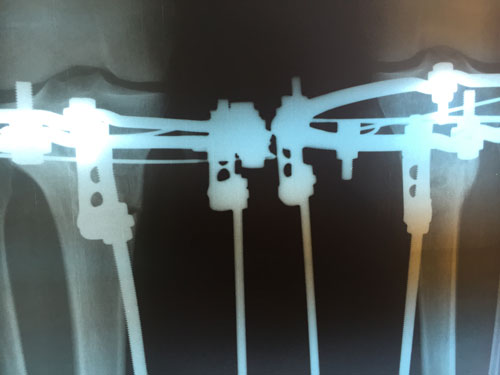

РЕНТГЕН ДО ОПЕРАЦИИ

рентген в 20 дней после операции.